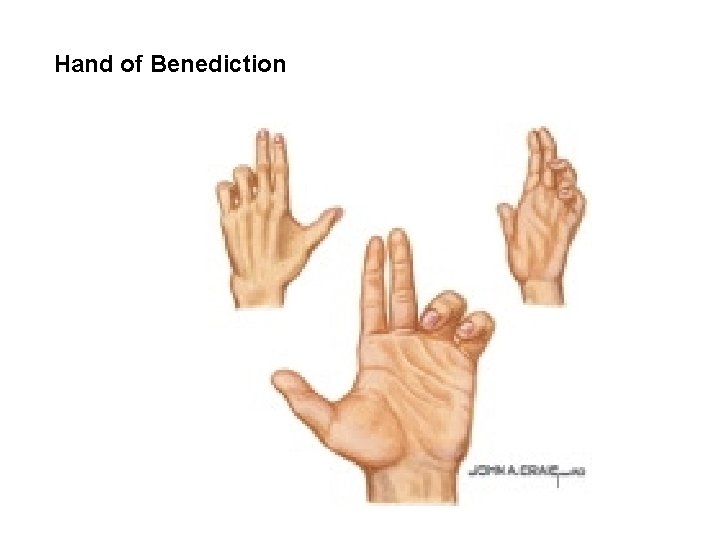

Hand of Benediction